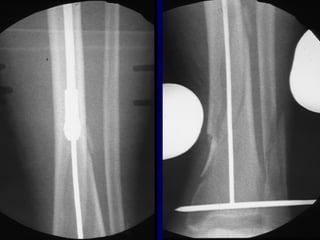

Technique • Screws placedon concave side of deformity.

Blocking (Poller) Screws •Functionally narrow im canal • Increase strength and rigidity of fixation

The Use ofPoller Screws as Blocking Screws in Stabilising Tibial Fractures Treated with Small Diameter Nails • 21 patients • All healed within 3-12 months • Mean alignment 1 degree valgus, antecurvatum 2 degrees. Krettek C, et al. JBJS 81B: 963, 1999

• Entry Sitefor Proximal fractures Critical • Reference is Lateral Tibial Spine

Proximal and DistalCases Courtesy of R. Winquist M.D. Seattle, Wa.